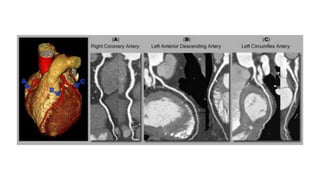

Abnormal Findings • White flecks( calcification ) and dark ( soft plaque ) , arrows are blockages